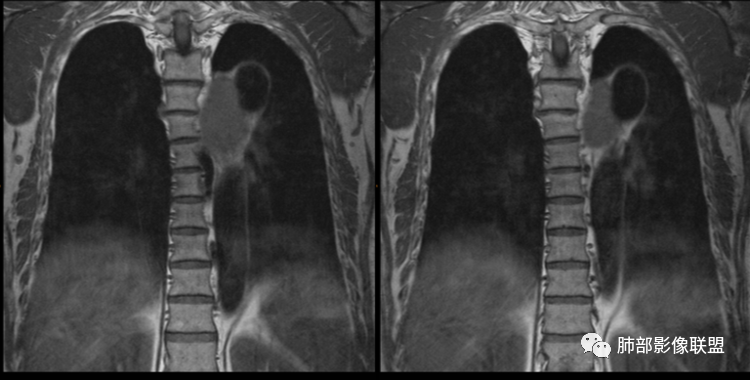

男性,43岁,体检发现后纵隔占位,边缘光整,CT示密度均匀,周围组织受压移位,无钙化囊变及脂肪组织,增强未见明显强化。MRI:T1示肿块信号较肌肉高,T2不均匀高信号。考虑为良性病变,第一是神经节细胞瘤,其次是支气管源性囊肿。

中年男性,无症状,后纵隔肿块,长径大矢状位于横径,质地偏软,塑形,等t1稍长t2,比较均质,增强轻微强化,与脊柱,主动脉,食管脂肪间隙存在,部分层面与脊柱相贴,骨质无改变,周围无肿大淋巴结,考虑神经源性肿瘤,节细胞神经瘤可能大,鉴别心包斜窦,淋巴瘤,淋巴管囊肿。